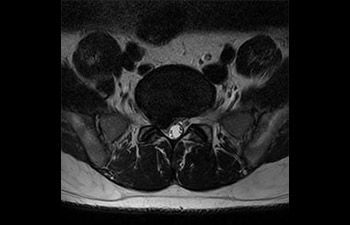

• Es una innovadora técnica de aceleración que no solo permite agilizar las secuencias, sino todo el estudio. • Implementación especial con la que las exploraciones en 2D y 3D pueden llegar a ser hasta un 50% más rápidas con una calidad de imagen prácticamente equivalente.1

• Se puede usar con todos los contrastes y con todas las regiones anatomías.

con Compressed SENSE